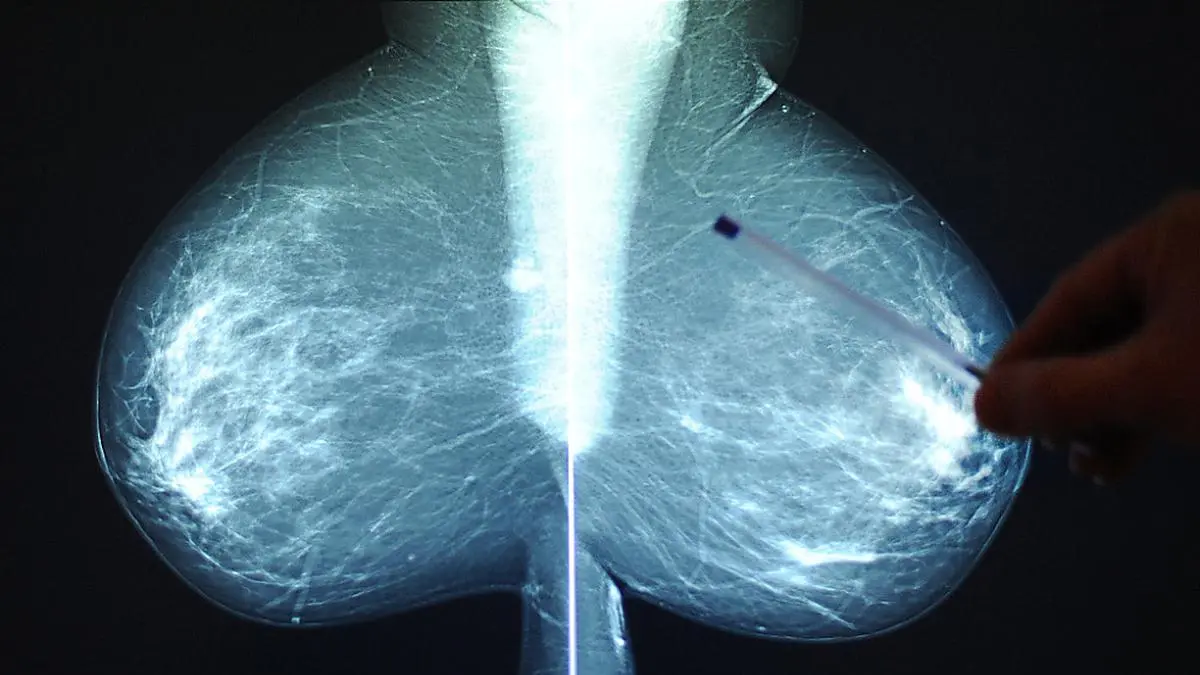

Brustkrebs-Früherkennungsprogramm hat keinen großen Effekt

2014 ist in Österreich das zuvor lange geforderte qualitätsgesicherte Brustkrebs-Früherkennungsprogramm samt Einladungen an Frauen zur Teilnahme eingeführt worden. Es sollte die Entdeckung von Mammakarzinomen in einem früheren Stadium bewirken. Doch eine neue Studie aus Salzburg bringt erhebliche Zweifel. Auf Ebene der Bevölkerung besserte sich gegenüber der Zeit vor dem Programm nichts.